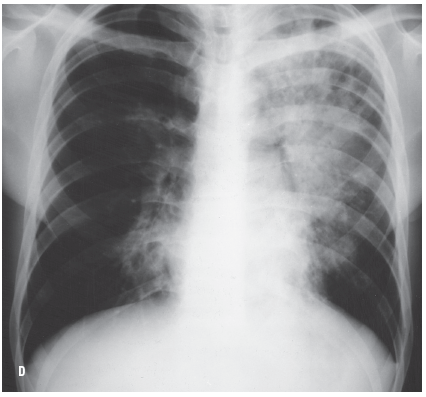

Blastomycosis can also masquerade as tuberculosis, as in the case of a 28-year-old man who had recently quit smoking and presented with a history of productive cough, mild hemoptysis, fatigue, fever, night sweats, and weight loss. A chest radiograph (C) showed disease process predominantly in the left upper lobe (white arrows) with infiltration as well as cavitation. A small area of infiltration is seen in the right hilar region. The clinical presentation and radiologic findings were consistent with tuberculosis. The patient failed to show clinical improvement with antibiotics, and a trial of antituberculous drug was started while results of sputum cultures were awaited. Twenty-six days after the patient’s initial visit, his chest radiograph (D) showed deterioration in both lungs. Sputum culture results were negative for Mycobacterium tuberculosis but positive for B dermatitidis. The patient was treated with ketoconazole; 2 months later, there was radiologic evidence of marked improvement.